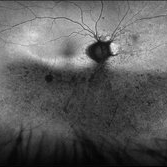

Retinitis Pigmentosa With Hemangioma CF

Dec 15 2016 by Manish Nagpal, MD, FRCS (UK), FASRS

Fluorescein angiography OS of a patient having retinitis pigmentosa with a hemangioma inferiorly.

Condition/keywords: hemangioma, retinitis pigmentosa